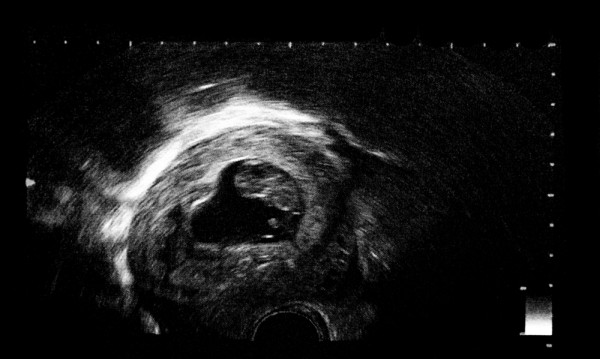

УЗИ

11-я неделя – это время первого запланированного скринингового обследования. Оно позволяет оценить рост и размеры ребенка, его жизнеспособность, способ прикрепления к стенкам матки, а также выявить возможные патологии.

Определить пол ребенка можно только с использованием современного высокочувствительного оборудования и при условии, что малыш займет удобное для просмотра положение. Обычно к этому сроку он уже располагается правильно – головой вниз.